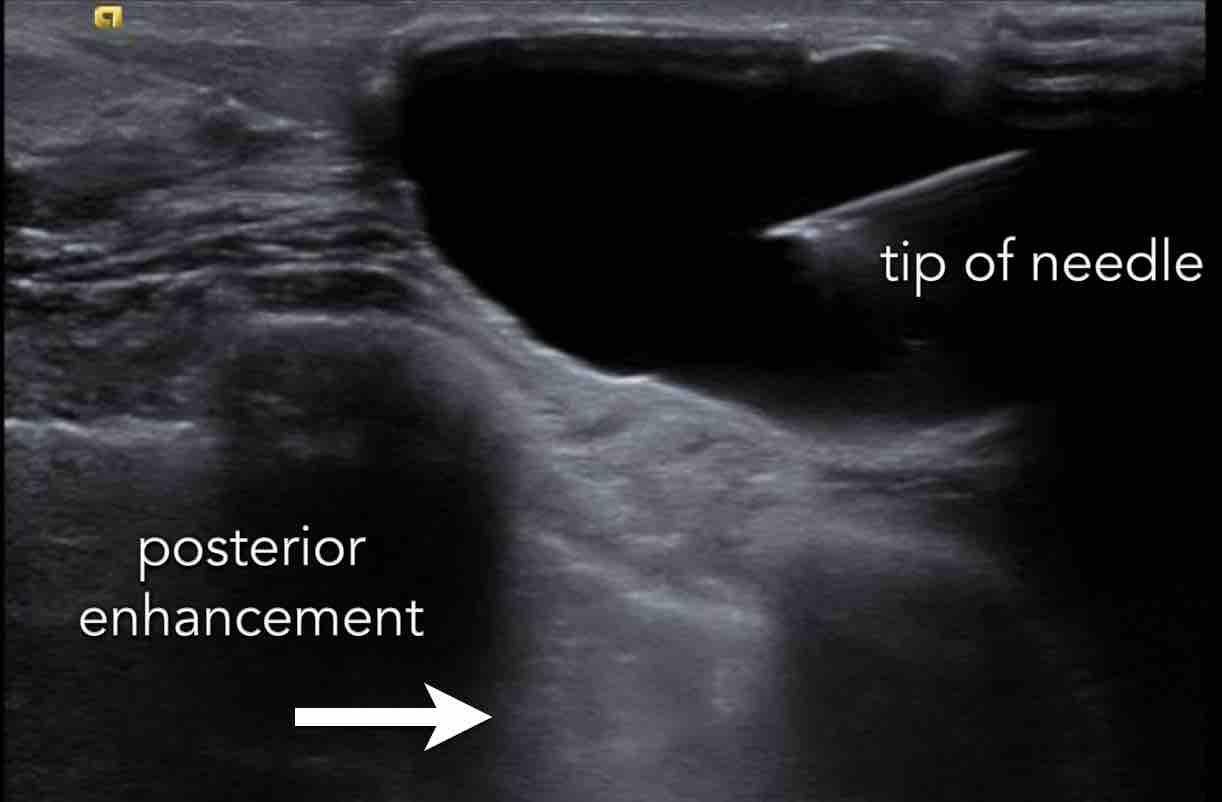

Đây là một nang nhiễm trùng khác, đã được chọc hút.

Chọc hút là một thủ thuật nhanh chóng và đơn giản.

Trong hầu hết các trường hợp, dịch hút ra có màu vàng trong suốt, nhưng cũng có thể có màu xanh lá hoặc nâu.

Không cần thiết phải xét nghiệm dịch hút ra.

Tuy nhiên, vẫn có tăng âm phía sau, khiến chúng tôi nghĩ rằng đây có thể là một nang.

Chọc hút đã được thực hiện và nang được hút hoàn toàn, đây là bằng chứng cuối cùng xác nhận chẩn đoán.

Cũng cần lưu ý hiện tượng tăng âm phía sau (posterior enhancement) — đây là dấu hiệu cho thấy cấu trúc này chứa dịch.